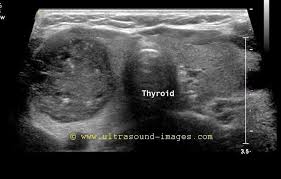

Idea Of Echographie de la thyroide PDF